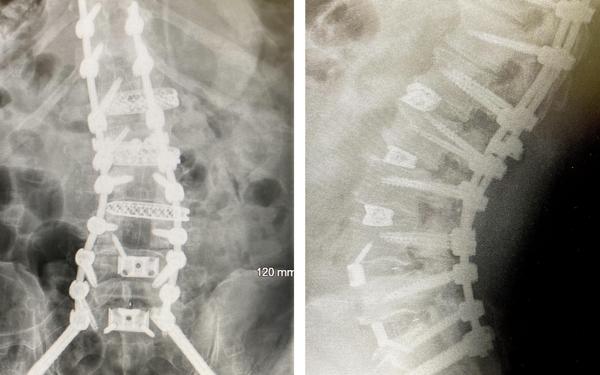

When I entered the hospital three weeks ago (tomorrow), the surgery was supposed to take 5.5 hours, but wound up taking 10 hours! There are five incisions - three on my left side, one in front, and the main one, 12” long, in my back. We were told that the first surgery failed,

and that four screws had worked loose, which is NOT supposed to happen! In any event, these x-rays will give you an idea what I look like on the inside now.